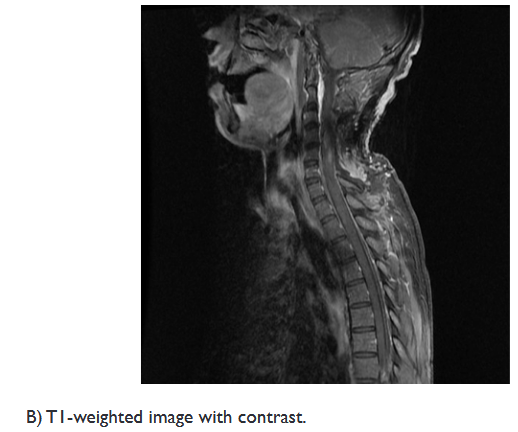

On examination, the muscle strength of the upper extremity was 2/5, and 3/5 in his lower extremity, with a positive Hoffman’s and Babinski’s signs. A spinal MRI revealed an intramedullary cystic mass, at level of C4, with ring enhancement after injection of gadolinium, associated with perilesional edema extending from the level of C2 to C7 (Figure 1).

Figure 1 Preoperative sagittal MRI of the cervical spinal cord.

Murphy et al. reported that the presentations of ISCA on MRI are similar to those of a cerebral abscess. In the early stages of infectious myelitis, MRI shows high-signal intensities on T2WI. The lesion reveals poorly defined enhancement on T1WI with contrast. One week later, the lesion becomes less diffusely hyper-intense on T2WI. The marginal enhancement is clearly defined on T1WI with contrast. Diffuse marginal cord edema was also noted.18